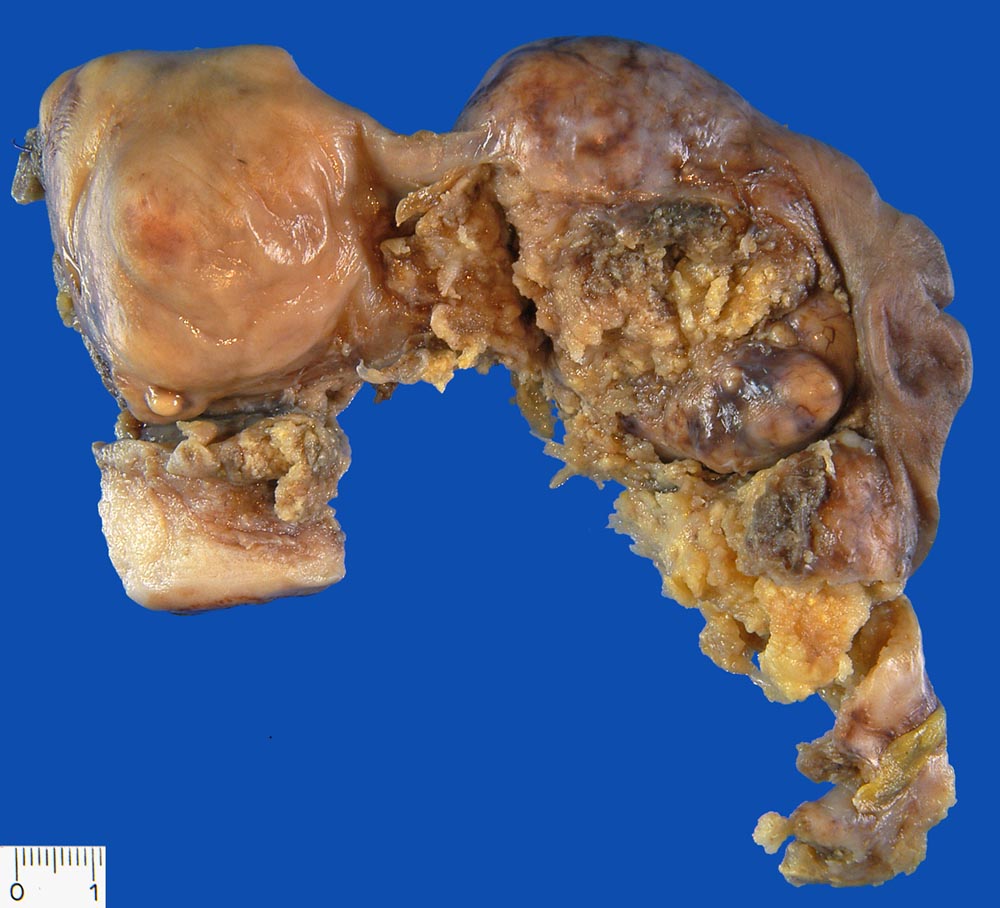

Serös papilläres Ovarialkarzinom

Uterus mit rechter Adnexe. Papillärer Tumor ausgehend vom rechten Ovar. Ausgedehnte Tumorinfiltration der Serosaoberfläche.

Serös papilläres Karzinom

Karzinom im kleinen Becken

Makroskopie